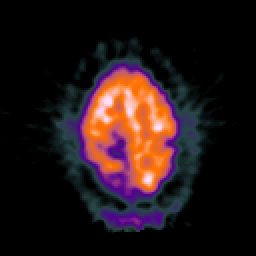

Glioma Overlay -- Slice #18

[Home][Help][Clinical] Slice 18